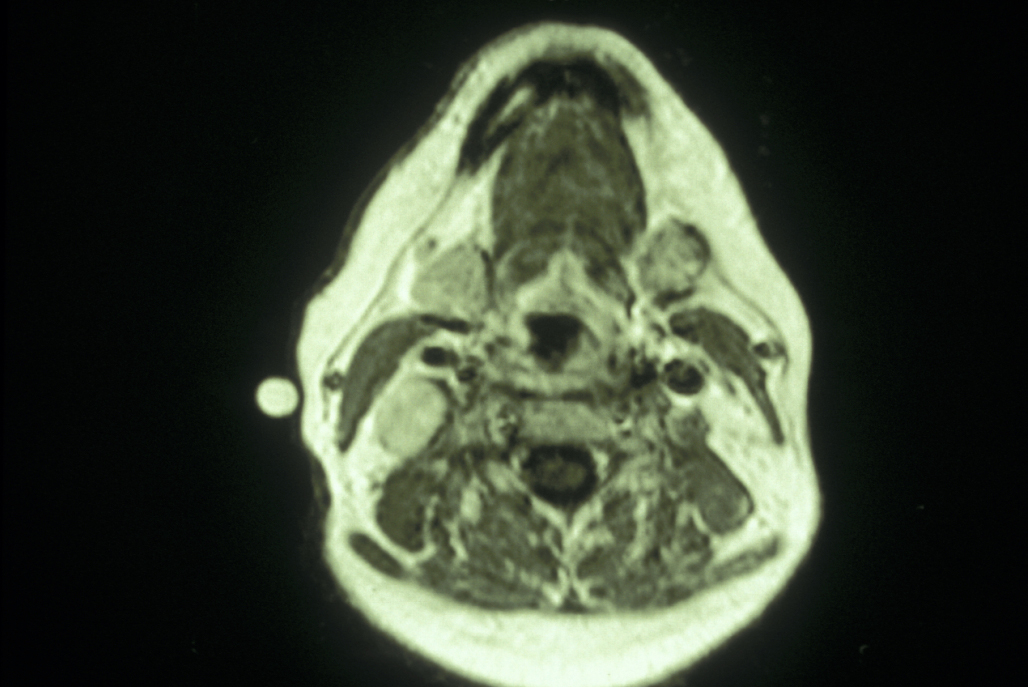

Paragangliomas - glomus vagale tumours are vagal paragangliomas arising from the mass of paraganglionic tissue within the perineurium of the vagus nerve just below the skull base. These may extend through the jugular foramen (aperture in the base of the skull). This is a slow growing mass in the upper neck, and symptoms are relatively late (pulsatile tinnitus, vertigo, deafness and pharyngeal pain). These tumours need to be investigated by MRI or CT scanning and should be excised because they are at the risk of spreading into the cranial cavity. These are extremely vascular tumours and as most of them are crossed by the internal carotid artery, there is a high level of risk of vascular injury.

Carotid body tumours - the carotid body tumour (glomus tumour) is the most common paraganglioma in the head and neck. These are uncommon tumours representing 0.6% of head and neck neoplasms and approximately 0.03% of all neoplasms. These tumours arise from the chemoreceptor bodies at the bifurcation of the carotid artery. Carotid body tumours can be distinguished on MRI or CT imaging from glomus vagule and glomus jugulare tumours (see below) because they tend to splay the internal and external carotid arteries, whereas the other two tend to displace the internal carotid artery anteriorly. There may be a clinical history of a slowly enlarging painless lump in the middle of the neck, this may be pulsatile. The lump will feel firm and rubbery, and it is classically described as being mobile from side to side, but not up and down (although this is not a particularly useful clinical sign in reality). The higher prevalence of carotid body tumours has been related to chronic hypoxemia from COPD (chronic obstructive pulmonary disease) and high altitudes. The sporadic form of carotid body paraganglioma is more common than the inherited variety and tends to occur more often in women. Familial tumours account for about 10% of all carotid body tumours and have an autosomal dominant mode with variable penetrance and higher incidence of bilateral tumours (which needs to be excluded with ultrasound scanning).

Carotid body tumours are extremely vascular tumours and hence biopsies should not be attempted. These tumours are characteristic on CT and MRI scans or by MRA (magnetic resonance angiography). These techniques may demonstrate widening (classic contrast and angiographic finding) of the carotid bifurcation (Lyre Sign). The majority of these tumours are benign although it is impossible to distinguish benign and malignant carotid body tumours on the basis of histology alone. Occasionally the tumour may transmit the carotid pulse or demonstrate a bruit or thrill. Because of its proximity to the carotid vessels and the X-XII cranial nerves, enlargement of the tumour may cause progressive neurological symptoms such as dysphagia (difficulty swallowing), odynophagia (distorted sense of smell) or hoarseness. There may be a history of symptoms suggestive of excessive catecholamine production (blood test for vanillylmandelic acid (VMA) levels; VMA is a metabolite of catecholamine) such as fluctuating hypertension, flushing and palpitations, but this is actually very rare.